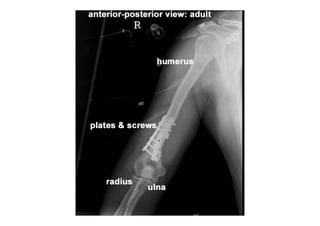

RADIOLOGIA DO

TRAUMA DO ESQUELETO

Referência: http://www.accessexcellence.org/RC/VL/